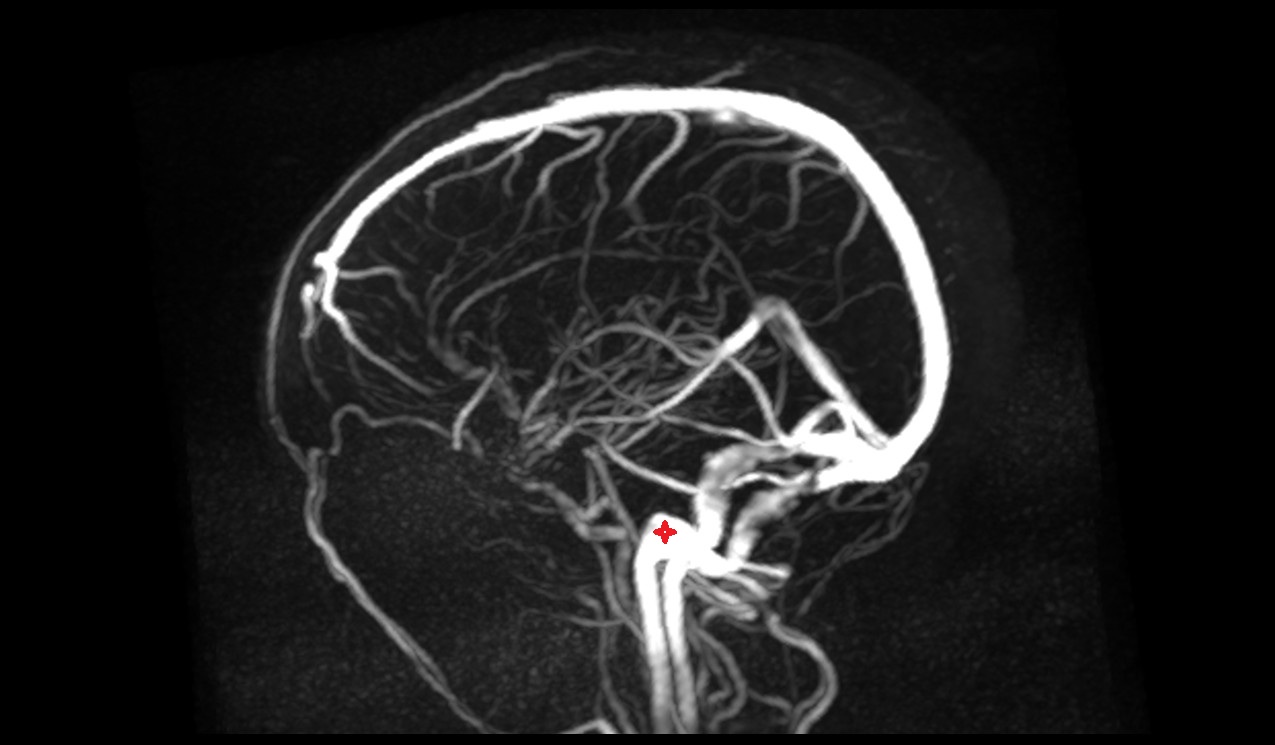

- Basilar artery

- Internal carotid artery

- Right vertebral artery

- Left vertebral artery

- Right Vertebral Artery (Intracranial Part)

- Left Vertebral Artery (Intracranial Part)